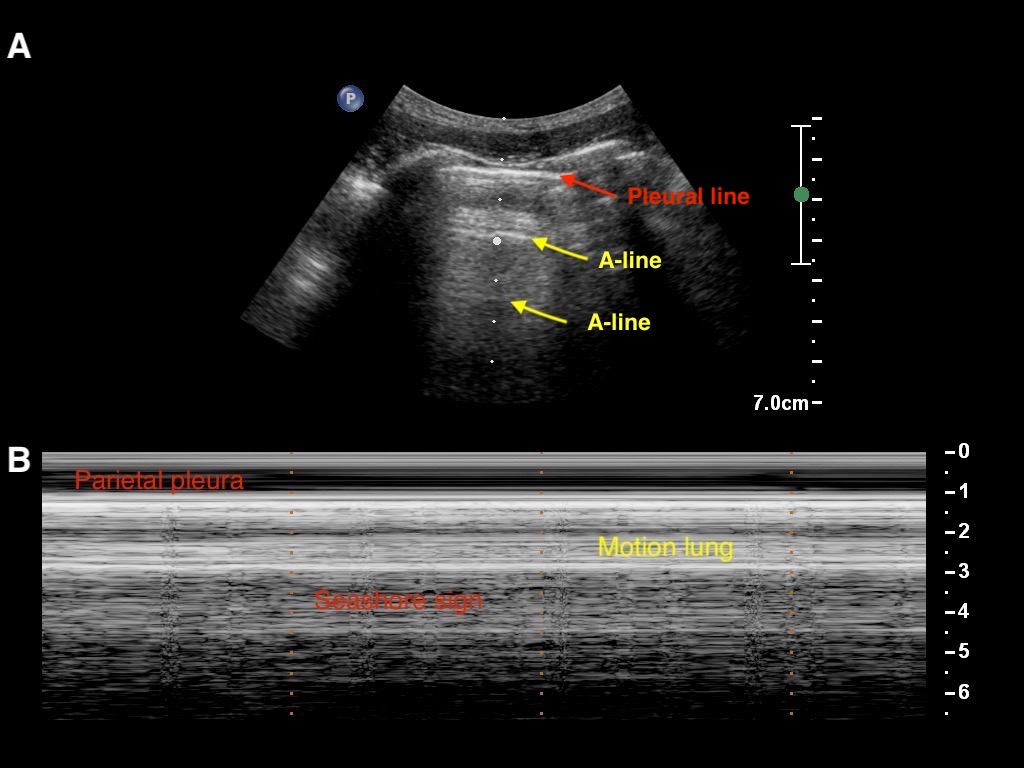

Artifacts

Pneumothorax